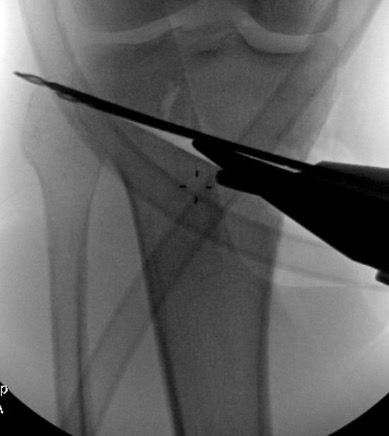

Consider lateral hinge 2 mm K wire

- 10 mm from lateral cortex

- distal to proximal

Oblique Osteotomy

- entry is 4 cm distal to joint line

- osteotomy must pass above tibial tuberosity

- aiming for proximal third of the fibula head

- to 10 mm of lateral cortex to avoid lateral hinge fracture

- stay 2 cm below the tibial plateau to avoid intra-articular fracture

- ensure osteotomy is parallel to joint line to avoid altering slope

- ensure complete posterior cortex

Guide pins for osteotomy and checking posterior slope

Osteotomy to within 1cm of the lateral cortex

Lateral 2 mm K wire - inserted distal to proximal 10 mm from lateral cortex